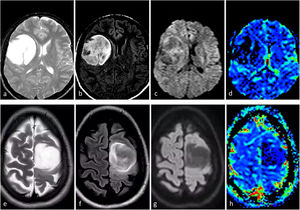

ImágenesLas imágenes características del glioblastoma consisten en una lesión expansiva-infiltrante con realce irregular prominente, necrosis central extensa y márgenes mal definidos. Con frecuencia se observan diferentes grados de hemorragia. Son habituales las zonas de edema de moderadas a grandes y el efecto de masa1–3,23. Son recurrentes la infiltración de la piamadre y el epéndimo44. Los componentes tumorales en T2w y FLAIR, no captantes, pueden ser radiológicamente visibles, aunque no suelen ser la parte predominante del tumor45,46. Son muy comunes las áreas de CBV claramente elevado y difusión restringida dentro del tumor captante47,48. Además, la detección de estas áreas hiperperfundidas/con difusión restringida más allá del tumor captante es útil para diferenciar el glioblastoma de las metástasis únicas49–51 (fig. 3).

Tres presentaciones típicas diferentes del glioblastoma IDH-wildtype en pacientes de entre 60 y 70 años. a-c) características paradigmáticas en imágenes axiales T1w poscontraste de tres pacientes diferentes, con márgenes irregulares, realce en anillo y necrosis extensa. d-f) FLAIR axial, T1w poscontraste y mapas de color del CBV de DSC-PWI. Extensa lesión infiltrante temporal izquierda en FLAIR (d) con realce nodular sólido asociado y sin necrosis (flecha en d), pero con CBV claramente elevado (círculo en f). g-i) FLAIR axial, T1w poscontraste y mapas de color de CBV de DSC-PWI. Lesión infiltrante temporal izquierda en FLAIR focal (g) con realce mínimo y ausencia de necrosis (flecha en h), pero con CBV claramente elevado (círculo en i).

CBV: volumen sanguíneo cerebral; DSC-PWI: imagen de perfusión dinámica; IDH: gen isocitrato deshidrogenasa.

En ciertos casos, el glioblastoma puede manifestarse sin necrosis clara y presentar predominantemente un patrón infiltrante. Estos tumores se caracterizan por mayores componentes no (o escasamente) captantes y mal definidos13. En estos tumores sin realce y no necróticos, la presencia de una clara restricción de la difusión o un aumento del CBV son de especial interés, ya que respaldan notablemente el diagnóstico de glioblastoma23,52 (fig. 3). En resumen, ante una lesión expansiva-infiltrante en un adulto mayor de 55 años, el neurorradiólogo debe buscar minuciosamente manifestaciones de un grado histológico 4 que sugieran altamente el diagnóstico de glioblastoma. En concreto, necrosis en T1w poscontraste, hipercelularidad en DWI e hipervascularización en DSC-PWI.